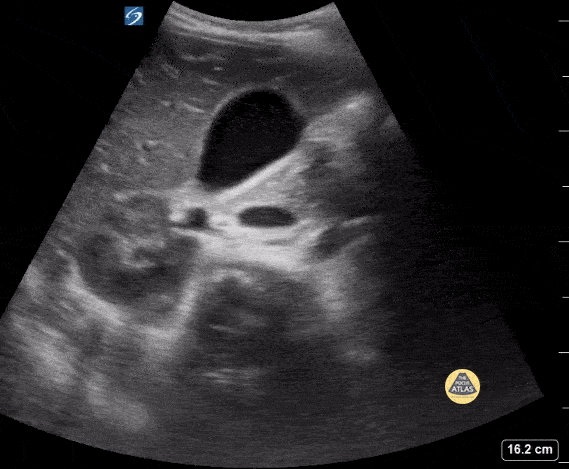

Peds-Biliary - Normal Gallbladder, Short Axis

16 yo with abdominal pain. POCUS shows a normal gallbladder in short axis. Contributor: Kathryn Pade, MD, Rady Children's Hospital San Diego